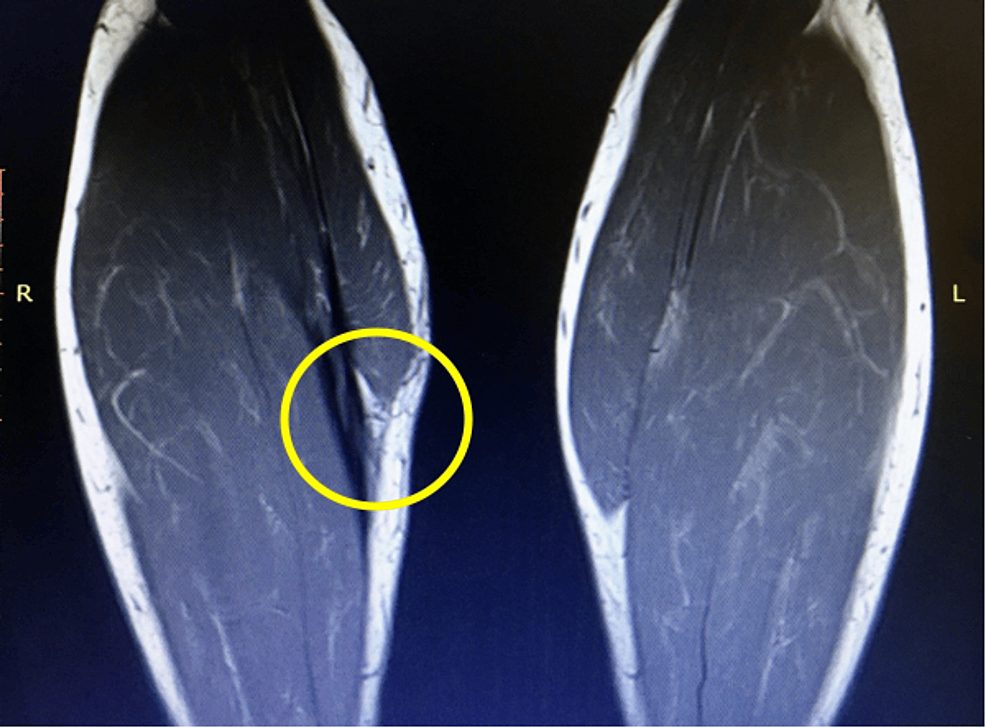

PPT MRI EVALUATION OF TENNIS INJURIES TENNIS ELBOW AND BEYOND What Is Tennis Leg Injury Tennis leg represents a myofascial or tendinous injury of the lower limb and, not surprisingly, is seen most frequently in tennis players. Learn how to diagnose, treat and prevent this injury with ultrasound, exercises and advice from a specialist. The injury is invariably associated with extensive bruising and swelling, and can be mistaken for a deep venous thrombosis. Learn how. What Is Tennis Leg Injury.